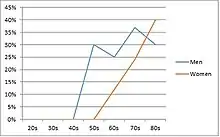

Epidemiological studies strongly support a relationship between age and cuff tear prevalence,[15][16][17] with the most common cause being age-related degeneration and, less frequently, sports injuries or trauma.[18]

Those most prone to failed rotator cuff syndrome are people 65 years of age or older; and those with large, sustained tears. Smokers, people with diabetes, individuals with muscle atrophy or fatty infiltration, and those who do not follow postoperative-care recommendations also are at greater risk. In a 2008 study the frequency of such tears increased from 13% in the youngest group (aged 50–59 y) to 20% (aged 60–69 y), 31% (aged 70–79 y), and 51% in the oldest group (aged 80–89 y).[19]

In an autopsy study of rotator cuff tears, the incidence of partial tears was 28%, and of complete rupture 30%. Frequently, tears occurred on both sides and occurred more often with females and with increasing age.[94] Other cadaver studies have noted intratendinous tears to be more frequent (7.2%) than bursal-sided (2.4%) or articular-sided tears (3.6%).[95] However, clinically, articular-sided tears are found to be 2 to 3 times more common than bursal-sided tears and among a population of young athletes, articular-sided tears constituted 91% of all partial-thickness tears.[95] Rotator cuff tears may be more common in men between the ages of 50–60, though between 70 and 80 there is minimal difference across genders.[92][96]